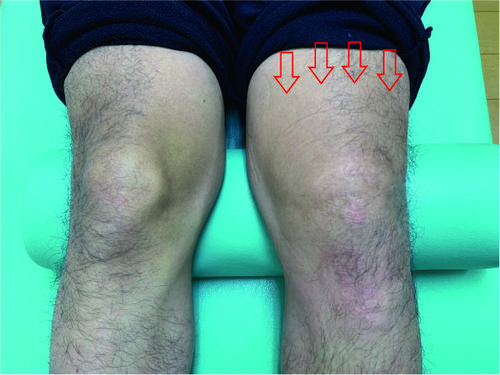

その他ではアメリカンフットボール中に、

スパイクで足の親指を踏まれたと御来院。

エコーで確認して骨折の疑いはなく、

長母趾伸筋腱の炎症と骨挫傷による関節腫脹。

sam MP.jpg